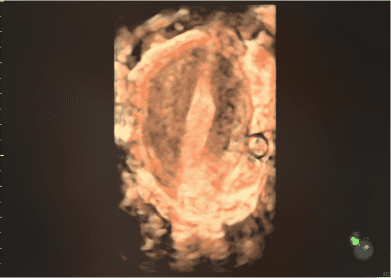

Imagens clínicas

Imagens 2D e 3D/4D de próximo nível

Imagens clínicas

Imagens 2D e 3D/4D de próximo nível